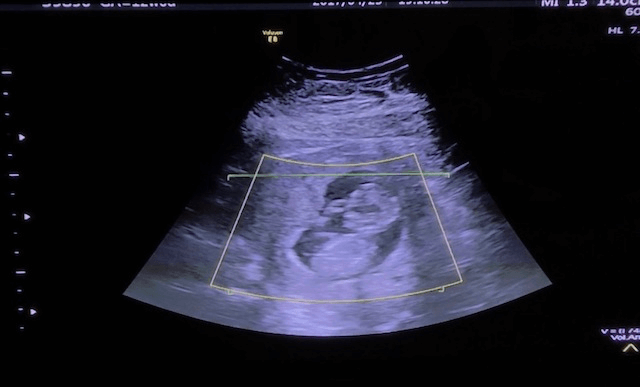

ナイスポーズ賞

受賞者:aiscream さん

エコー写真撮影時のエピソード(妊娠16週目:16w0d)

初めての妊娠。

どんどん大きくなる赤ちゃんの姿を楽しみに

待ちに待った検診 (o^^o)

元気な心臓の音を聞かせてくれて、

エコーも終盤になった頃

やっほー♪またねー♪

と言わんばかりに赤ちゃんが右手を上げて手を振ってくれたときの1枚です♡♡

編集部のコメント

本当にお腹の中から「また会えたね-!」「また会おうね-!」って手をふっているようなお写真ですね!健診に行くのがますます楽しみになる気持ちが伝わってくる一枚でした。